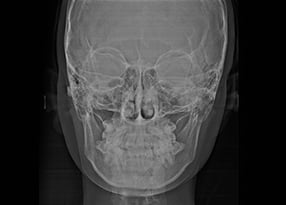

2. 精密検査

適切な治療法や正確な治療期間、費用などを決めるには、現状を細かく把握するための精密検査が必要です。お口やお顔の写真撮影、型取り、レントゲン検査などを行います。

矯正治療は、歯並びを整えるだけでなく、顔全体のバランスを考えることが大切です。歯の位置や角度は、顎の骨格や筋肉の動きと密接に関わっており、歯だけを動かしても、顔全体の印象や口元の調和がとれない場合があります。そのため、精密な解析機器を用いて頭部や顎の位置関係を立体的に測定し、骨格レベルでのバランスを数値化して分析しています。治療前後のデータを比較することで、口元の位置や輪郭の変化を客観的に確認でき、見た目の印象を左右する要素を科学的に把握しながら治療を進めます。

また、こうした骨格分析の結果を踏まえて、歯の移動量や方向をシミュレーションし、機能的な咬み合わせと自然なフェイスラインの両立をめざしています。歯並びの美しさだけでなく、骨格からととのえることを意識した治療計画を立てることで、治療後の表情や横顔の印象まで含めた総合的なバランスを整えます。見た目と機能のどちらも大切にした矯正治療を心がけています。